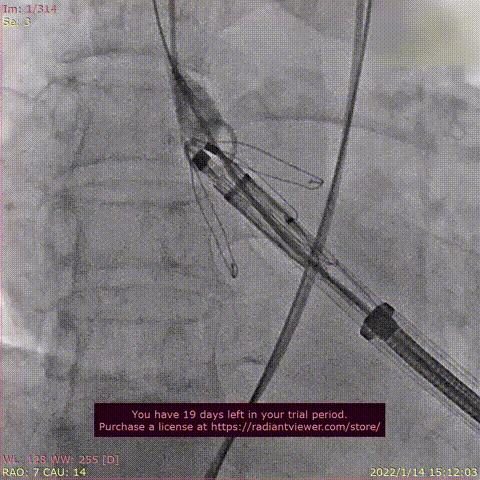

瓣膜释放过程

术后DSA影像图